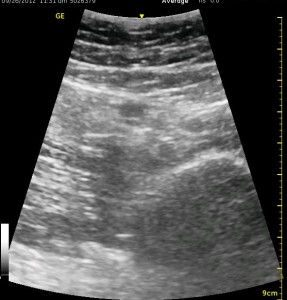

The image above is not an obvious one, and I did that on purpose. You have to get used to the idea that you will not always have a ‘super distinct’ image with this approach, and you will often need to use a number of additional clues to find your target and then to put local around it. I think the only way to really get a handle on being able to identify the basic elements is to look at several images over and over, so I have provided several below for you to use for practice. Note that the sciatic nerve will ‘poke out’ from behind the femur to different degrees depending on your orientation to the femur as well as to how far up or down the femur you go. It will be seen more if you are proximal. See how well you can identify the structures in the images below.